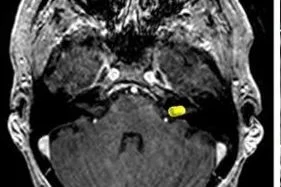

Μηνιγγίωμα: Τύποι, Συμπτώματα, Διάγνωση, Θεραπεία, Κίνδυνος Κακοήθειας και Νέες Εξελίξεις 2026

Αυτό το άρθρο προσφέρει μια ολοκληρωμένη επισκόπηση για τα μηνιγγιώματα, του πιο κοινού πρωτοπαθούς όγκου εγκεφάλου στους ενήλικες. Εξερευνά βασικές πτυχές όπως την προέλευση του …